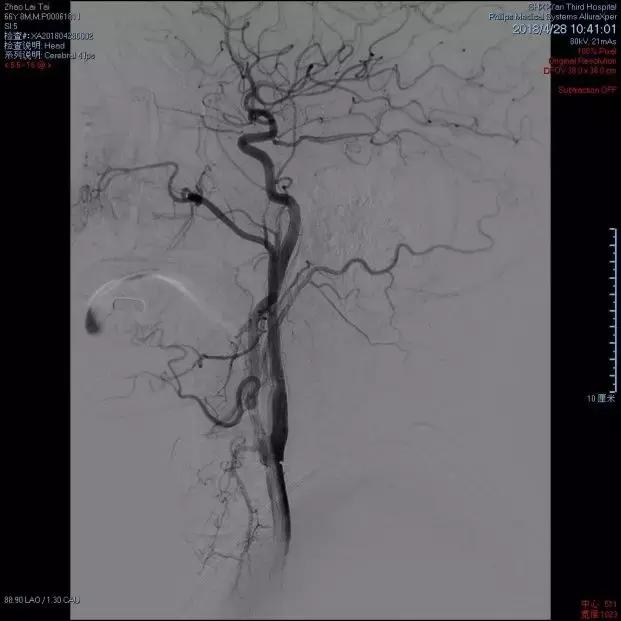

术后DSA提示左侧颈内动脉通畅

术后DSA提示左侧颈内动脉通畅 ,远端血供良好